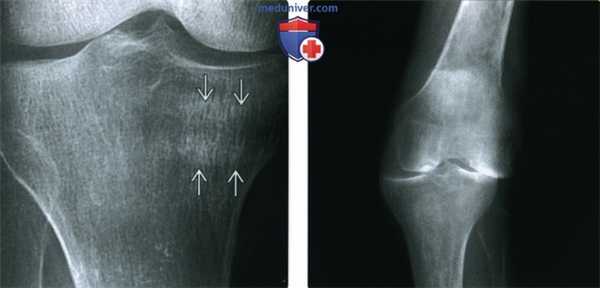

(Слева) Рентгенография в ПЗ проекции: выраженная остеопения и умеренное сужение медиального отдела сустава у пациента с РА и впервые возникшей болью. Также обратите внимание на две склеротичные линии в структуре медиального мыщелка большеберцовой кости. Они являются диагностическими признаками патологического перелома.

(Справа) Рентгенография в ПЗ проекции является классическим методом исследования при РА. Визуализируются общее сужение суставного пространства и выраженная остеопения. Кроме того, имеется слабость связок, что определяется по медиальному смещению большеберцовой кости относительно бедренной кости. Также обратите внимание на характерную вальгусную деформацию коленного сустава.